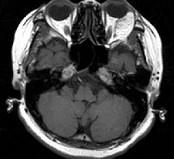

女,52岁,左眼球突出二十余年,T、T均正常,影像检查如图所示,应诊断为()A.错构瘤B.脂肪瘤C.畸胎瘤D.血管瘤E.炎性假瘤

问题 女,52岁,左眼球突出二十余年,T、T均正常,影像检查如图所示,应诊断为()

选项 A.错构瘤 B.脂肪瘤 C.畸胎瘤 D.血管瘤 E.炎性假瘤

答案 A